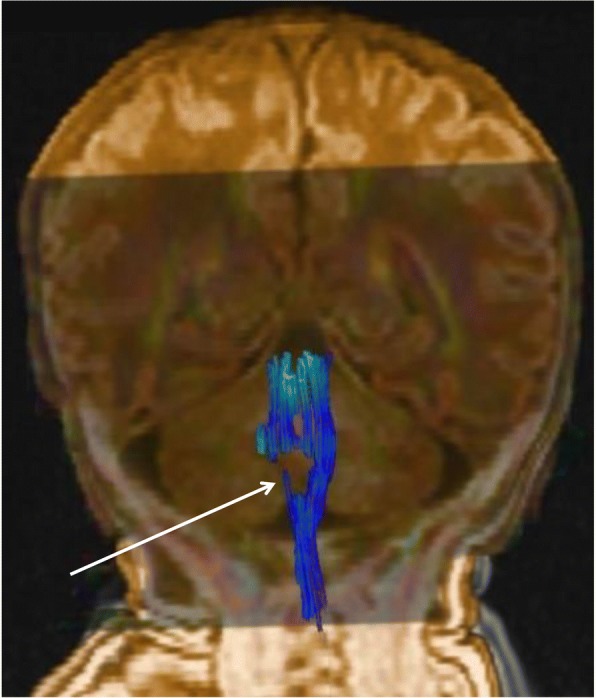

Fig. 4.

Fibre tracking using diffusion tensor imaging showing the section of the right lateral and median sensorimotor fascicles (white arrow)

In our patient, the initial decision for endoscopic surgical treatment was taken before MRI with fibre tracking demonstrated the unilateral medullary defect. However, neither this treatment nor CPAP, which can potentiate the results of an endoscopic procedure [4], prevented rapid reintubation. Several elements were taken into account in the multidisciplinary decision to limit curative care. The prognosis of brainstem disconnection is generally very poor, with respiratory failure occurring soon after support is removed. Death generally occurs in the first 2 months following birth, but cases of prolonged survival under chronic respiratory assistance have occasionally been described [22, 30]. Indeed, functional respiratory outcome is very poor in the event of congenital BVCP associated with major underlying comorbidity, with resolution of the vocal cord immobility in only 14% of patients and decannulation after 2 to 3 years in 25% [3, 31]. More recently, survival without mechanical ventilation has also been reported; however, gastrostomy was systematically needed, as well as tracheostomy at times [17, 19]. No or minimal achievement of developmental milestones has been noted in children with large defects [17]. In our case, characterized by a rather well-circumscribed, unilateral defect, tractography was particularly useful for reconstructing the course of the fibre tracts within the brainstem [32]. This microstructural analysis highlighted a section with several bundles, including the corticospinal, spinothalamic and spinocerebellar tracts, and the medial lemniscus. In addition, the topography of the lesion suggested the involvement of parts of the spinal tract of the right trigeminal nerve, the right nucleus tractus solitarii, the right cuneiform nucleus and the medullary reticular formation. In our patient, the BVCP also expressed the involvement of the ambiguus nuclei, which intervene in the motor innervation of the laryngeal muscles and adjoin the median raphe at the lower part of the medulla. Thus, relatively small lesions of the brainstem can have dramatic consequences, as nicely expressed by Boltshauser et al.: “small lesions-big problems” [19]. These authors reported on two children, aged 19 months and 32 months, with unilateral or asymmetrical defects. The examinations confirmed the multiple and major consequences of these lesions, in particular swallowing impairment, cranial nerve deficits, hemiparesis, and motor, speech and cognitive delays [19].